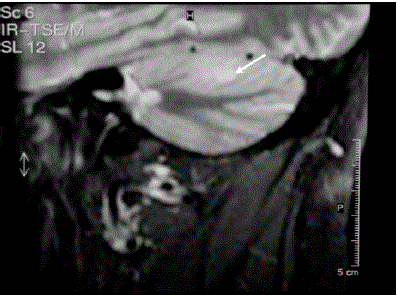

Figure 5. Craniospinal magnetic resonance imaging demonstrates a cerebellar haemangioblastoma (white arrow).